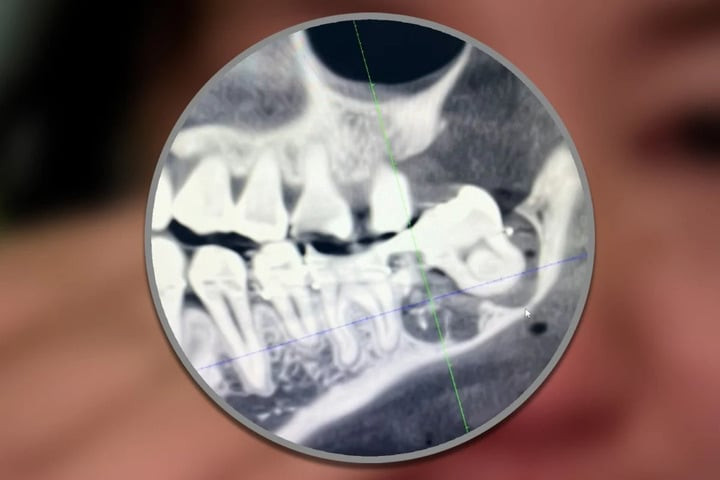

Răng khôn của cô Wu bị các bác sĩ Bệnh viện Thành phố An Khánh nhổ nhầm

Cô Wu, 34 tuổi, cư trú tại tỉnh An Huy, Trung Quốc, đã đến Bệnh viện Thành phố An Khánh vào ngày 12/3 để thực hiện nhổ răng khôn. Tuy nhiên, bác sĩ đã sai sót khi loại bỏ nhầm chiếc răng bên cạnh vẫn còn khỏe mạnh, sau đó cố định lại vào vị trí cũ. Khuôn mặt của cô sưng to, kéo theo những cơn đau kéo dài nhiều ngày.